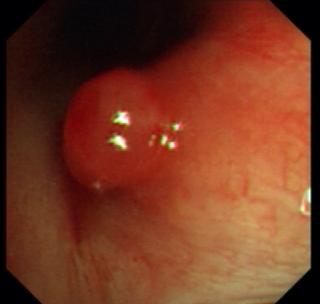

Once patients are suspected to have lung cancer or TB with X-ray or CT, bronchoscopy is followed-up from radiological imaging. Bronchoscopy is used as one of the invasive tool to directly detect the disease since 1960s [4]. Fig. 1 shows an example of normal tissue, TB and cancer. In bronchoscopy, usually we can observe that invasive TB, the lumen surface suffers from inflammatory change with hyperemia, edema and ulceration. Lung adenocarcinomas grow extraluminally and lead to lumen stenosis without affecting mucosal surface of lumen. Therefore, the mucosal surface of lumen is relatively smooth. However, squamous lung cancers always form intruding nodules and are difficult to be differentiated from TB granuloma visually. Computational aid is therefore needed in bronchoscopy, especially for lesion discrimination and targeting. Accurate targeting the disease area could significantly reduce the biopsy trauma and increase diagnostic accuracy [5].

Figure 1: A bronchoscopy image of normal (a), TB (b) and cancer (c)